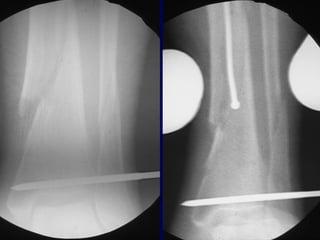

Technique • Screws placedon concave side of deformity.

• 56.

Blocking (Poller) Screws •Functionally narrow im canal • Increase strength and rigidity of fixation

The Use ofPoller Screws as Blocking Screws in Stabilising Tibial Fractures Treated with Small Diameter Nails • 21 patients • All healed within 3-12 months • Mean alignment 1 degree valgus, antecurvatum 2 degrees. Krettek C, et al. JBJS 81B: 963, 1999

• 58.

• Entry Sitefor Proximal fractures Critical • Reference is Lateral Tibial Spine

• 63.

Reduction of DistalTibial Fractures • Distractor • Joy Stick • Fibular Plating • Calcaneal Traction

Proximal and DistalCases Courtesy of R. Winquist M.D. Seattle, Wa.